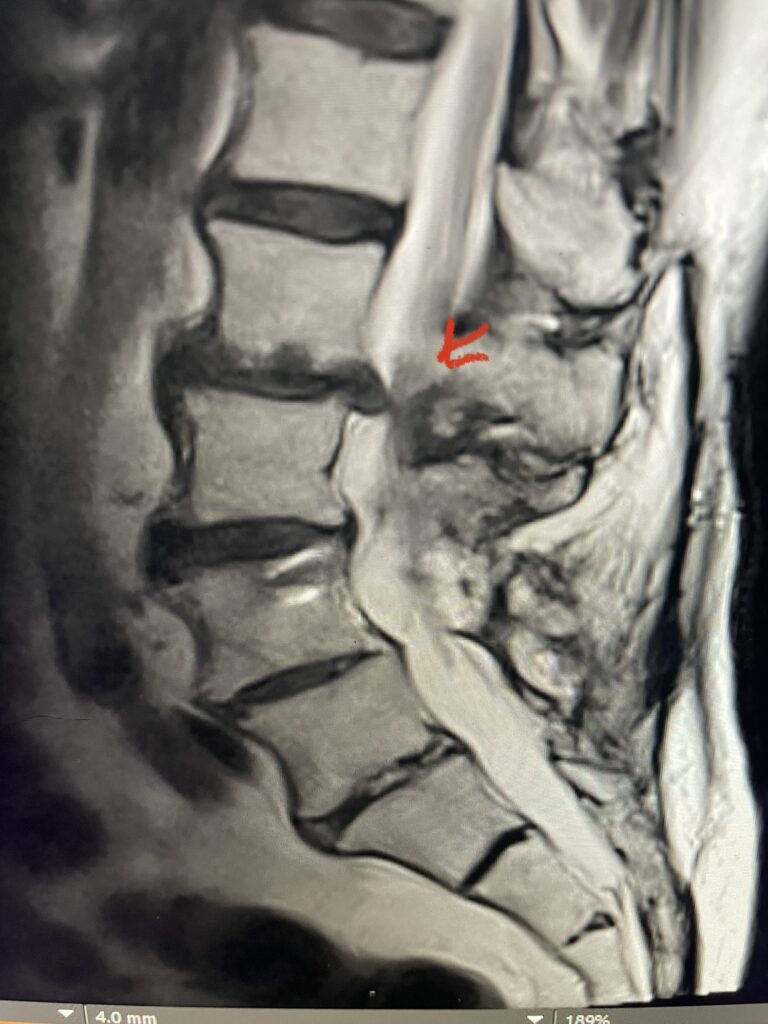

The actual structural cause of lumbar thecal sac compression can vary in degenerative spondylolisthesis and stenosis. The culprits are commonly thickened ligamentum flavum or severe facet […]

After 25 years in practice, I still find it challenging, but quite rewarding: removing degenerative material off the dural membrane in the lumbar spine. Some people […]

Nervous tissue is soft. The thecal sac is surrounded by a rigid bony ring which forms the spinal canal. Any mass that fills the very small […]